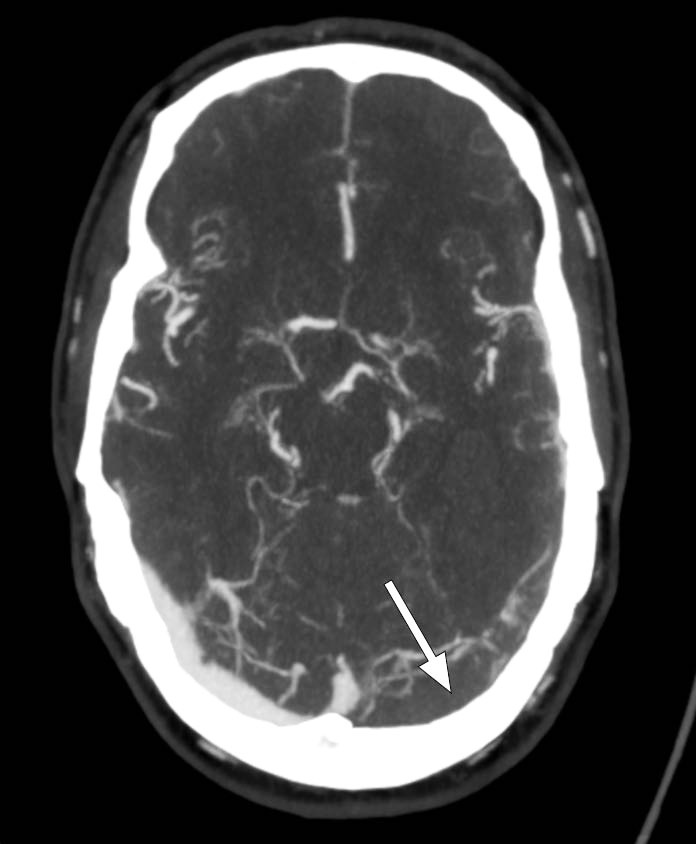

Ved innkomst fremsto han forvirret, søvnig og med afasi. CT caput avdekket intracerebral blødning i venstre temporallapp, og pasienten ble overflyttet til universitetssykehus for observasjon. Ved ankomst der var pasienten våken, men desorientert og hadde afasi uten andre fokalnevrologiske utfall. Han skåret 4 poeng på National Institutes of Health Stroke Scale, forenlig med et mindre hjerneslag. Kontroll-CT caput uten kontrast viste uendret størrelse av hjerneblødningen, og det ble reist mistanke om hemoragisk venøst infarkt grunnet tegn til cerebral venetrombose (figur 1). Supplerende CT-venografi viste manglende kontrastfylning av sinus transversus og sinus sigmoideus på venstre side, som bekreftet diagnosen (figur 2). Det ble samme dag startet behandling med lavmolekylært heparin i form av dalteparin 100 IE/kg to ganger daglig.